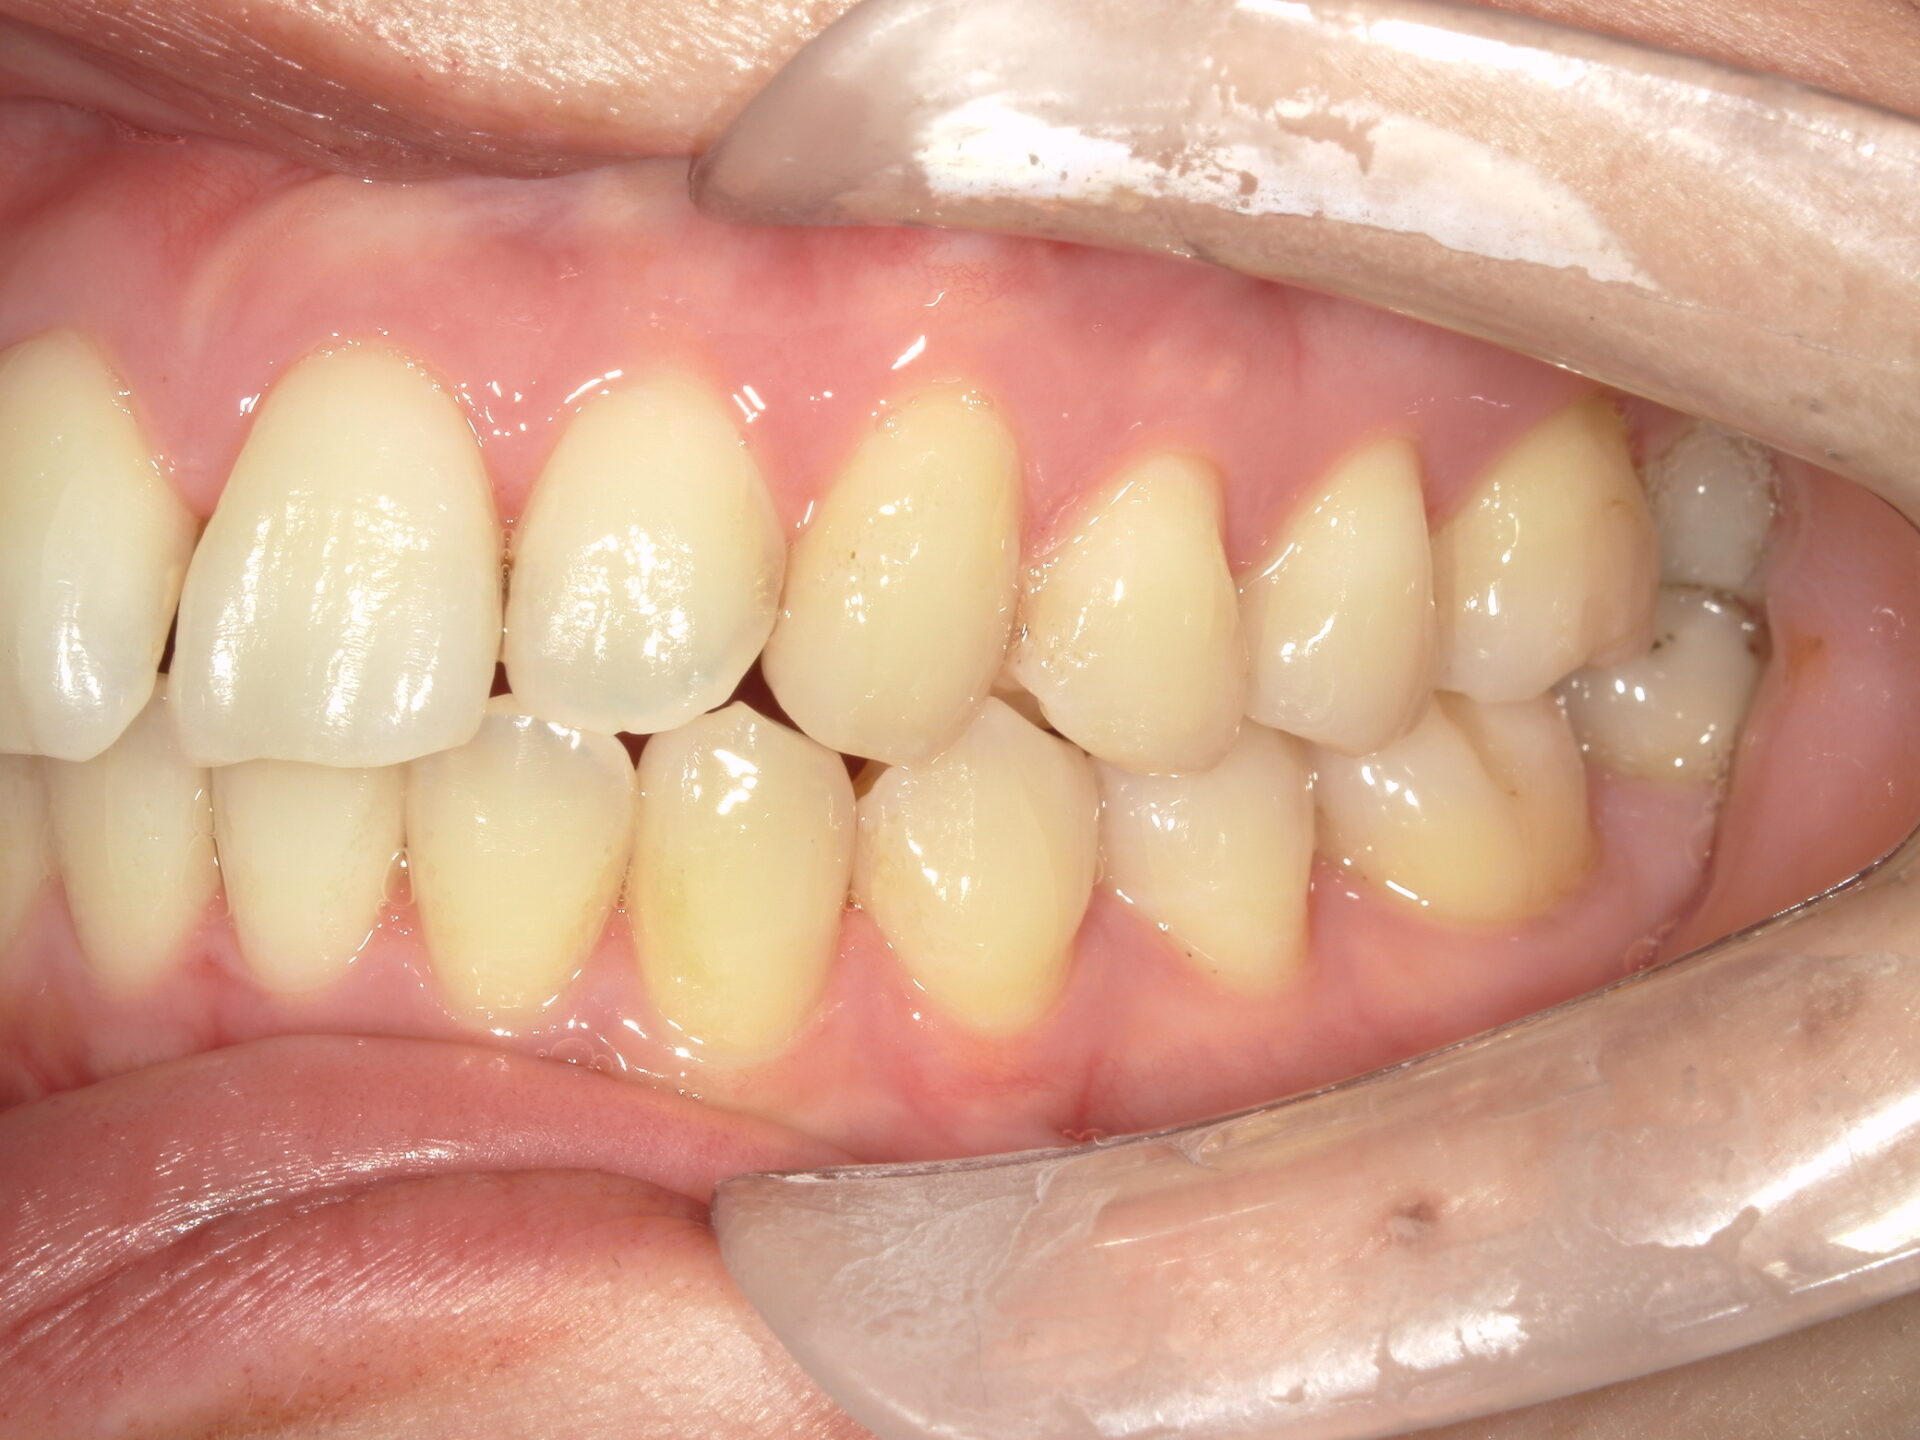

after

患者さんの年齢 20代 女性 症状 ガタガタを治したい 治療内容 マウスピース矯正治療 費用 90万(税抜) 治療期間・回数 治療期間2年、通院回数10回 メリット 笑顔が綺麗 デメリット・リスク 期間がかかることがある - マウスピース矯正